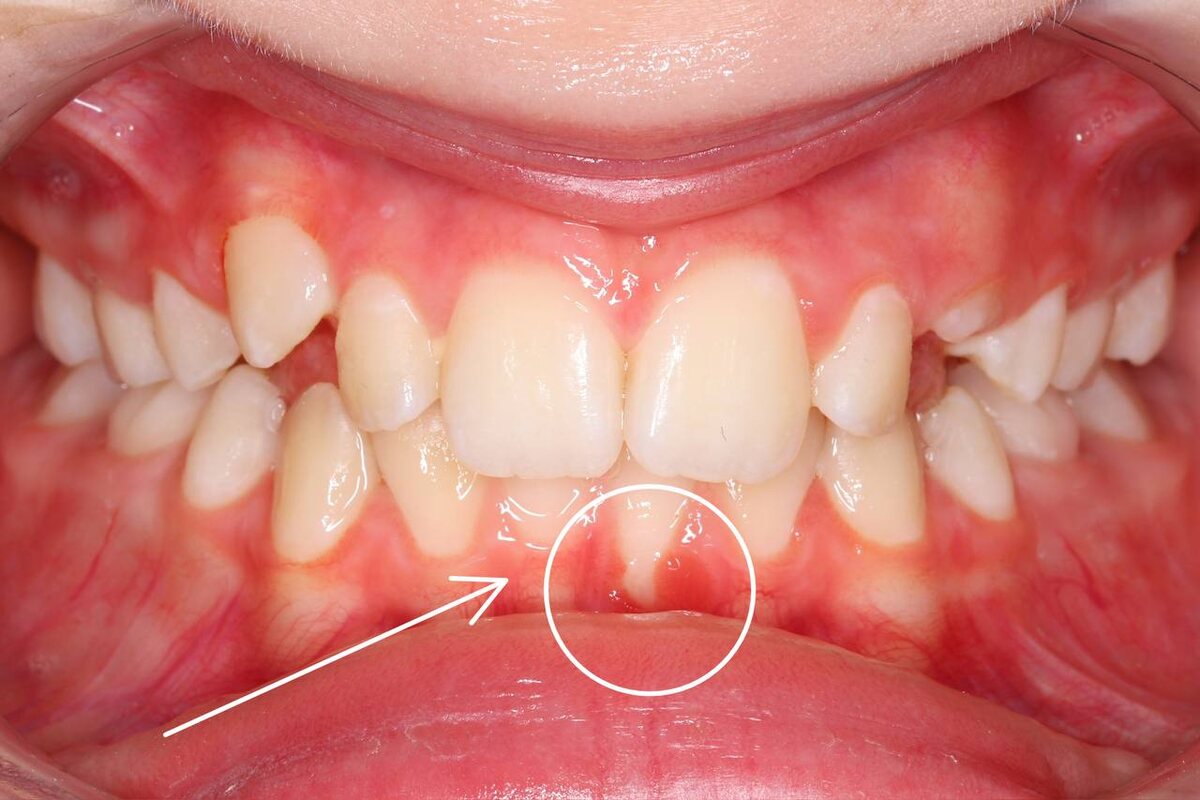

Исключение из правила на фото - если уздечка уже приводит к травме десны, пародонта - ждать нельзя. 🚫

Здесь мы видим рецессию у ребенка в зоне резцов - подрезать можно как только заметили!